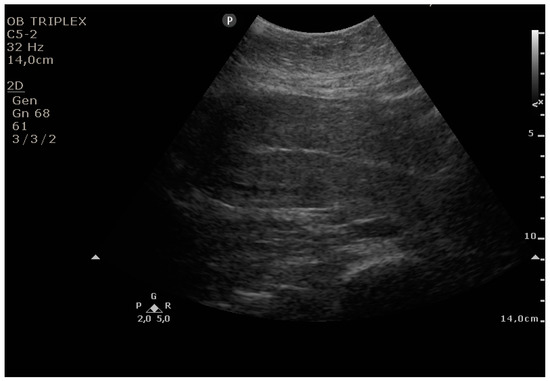

The PUUS method evaluates the proportion of the endometrial length occupied by blood or debris, as follows (Figure 1, Figure 2, Figure 3, Figure 4 and Figure 5):

Grade 1: less than a one-quarter of the endometrial length occupied by blood or debris;

Figure 2. Grade 1: less than one-quarter of the endometrial length occupied by blood or debris.